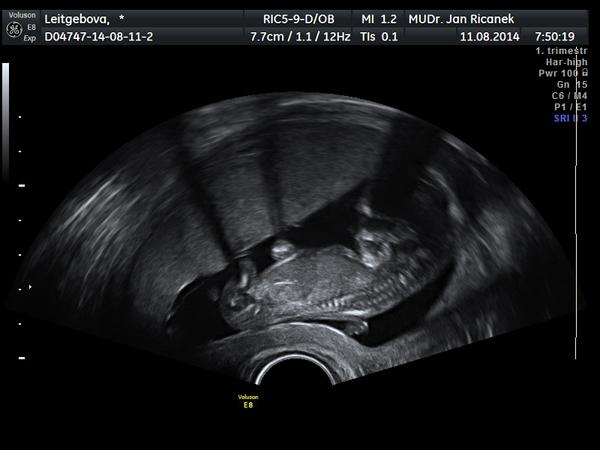

Ahoj holky moje, tak jsme doma,, juchů buší nám jako o život, podle UTZ jsme 7+3, podle počítání dle OPU 7+0, 29.8. už budu mít 1.poradnu u své doktorky, máme se rozhodnout ohledně těch testů na vývojové vady, v brně to dělají vše v 1 den výsledky jsou večer,nebo u své doktorky v 10.tt krev a ve 12.tt UTZ a pak se to vyhodnotí rozdíl cenový 1500,-/1000,- akorát mám zvětšený levý vaječník má asi 8 cm, to je prý to homonál.stimulací,mělo by se to postupně stahovat a zmenšovat, ale kdyby byl problém - bodavá bolest, něco jako kolika okamžitě na pohotovost.

@bubulina1983 No paráda, moc gratuluju, krásná fotečka 🙂

@bubulina1983 ahoj, no páni, to je úžasná fotka 🙂 moc gratuluji 🙂 je dobře, že sis došla ke své doktorce. Alespoň víš, co a jak a nemusíš se strachovat. Taky bych se přikláněla k testům v Brně. Takový rozdíl co se týká financí to opravdu není a alespoň budeš mít výsledky hned a nebudeš muset zase na něco čekat. A to přeci víš, jak se to čekání vleče 😀

@elisc + @luca16 + @andreee86 + @debee - holky díky moc za podporu, včera mi spadl balvan ze srdce, srdíčko ťukalo a doktorka se mě ptá vidíte to tady, ještě se ověřovala jestli to taky vidím, byla strašně hodná, vzala mi stěry a za 3 týdny už mám 1.poradnu 😀 no s těma testama uvidíme, něco si o tom přečtu a apk se rozhodneme..

@bubulina1983 Krásná fotečka!!! Gratuluji mamino!!!